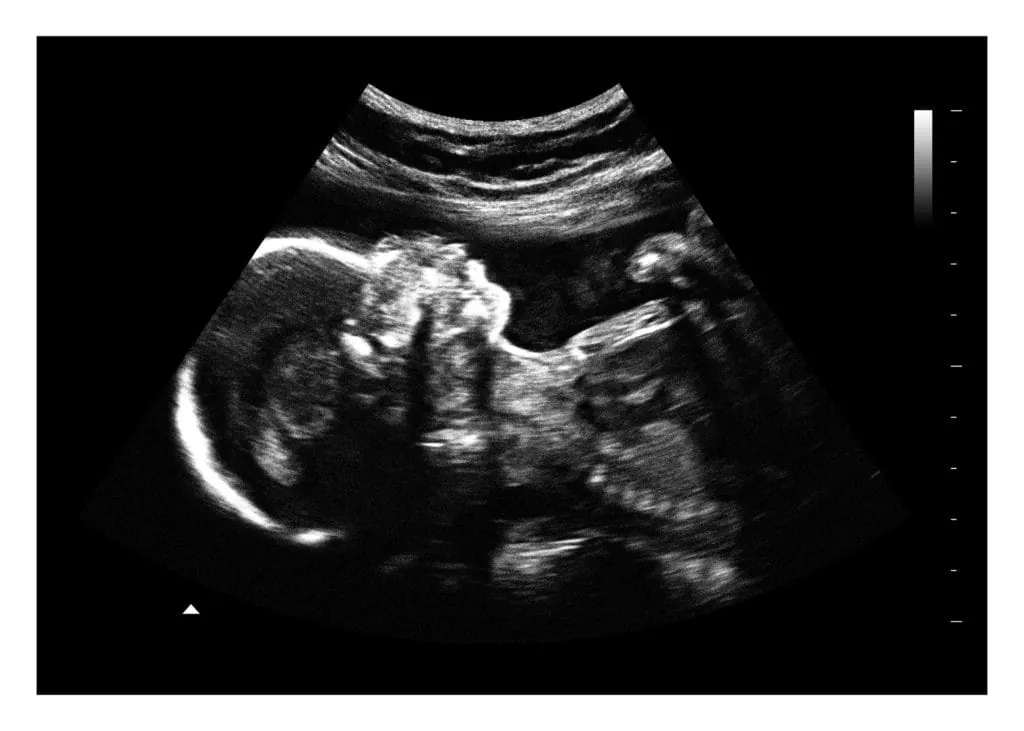

Ultrasound at 24 Weeks: What Is Checked?

⭐ Ultrasound at 24 Weeks: What Is Checked?

A growth scan or detailed ultrasound at this stage may evaluate:

1. Baby’s Measurements

• Head circumference (HC)

• Abdominal circumference (AC)

• Femur length (FL)

• Estimated fetal weight (EFW)

2. Organ Development

Assessment of:

• Heart structure and heartbeat

• Kidneys, bladder

• Stomach, intestines

• Lungs

• Spine and limbs

3. Fetal Movements

Observing:

• Limb movements

• Breathing motions

• Opening and closing of hands

4. Placenta

• Location (anterior, posterior, low-lying)

• Thickness

• Blood flow (Doppler if needed)

5. Amniotic Fluid Level (AFI)

6. Cervical Length (if needed)

For mothers at risk of preterm labor.